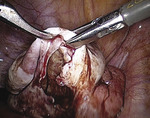

Delikatnie wsunięto pod lewy jajnik rurkę ssąco-płuczącą wprowadzoną przez lewy trokar. Następnie uniesiono przydatki lewe zrośnięte z blaszką tylną więzadła szerokiego. Po uwidocznieniu zrostu jajnika z otrzewną ruchem piłującym na tępo uwolniono zrosty narzędziem wprowadzonym przez przeciwległy port (ryc. 2). Podczas uwalniania zrostów z jajnika wylała się treść o barwie czekoladowej, którą odessano (ryc. 3). Po uwolnieniu zrostów („postawieniu” przydatków) i zbadaniu wnętrza torbieli zdecydowano się na zabieg oszczędzający (wyłuszczenie torbieli).